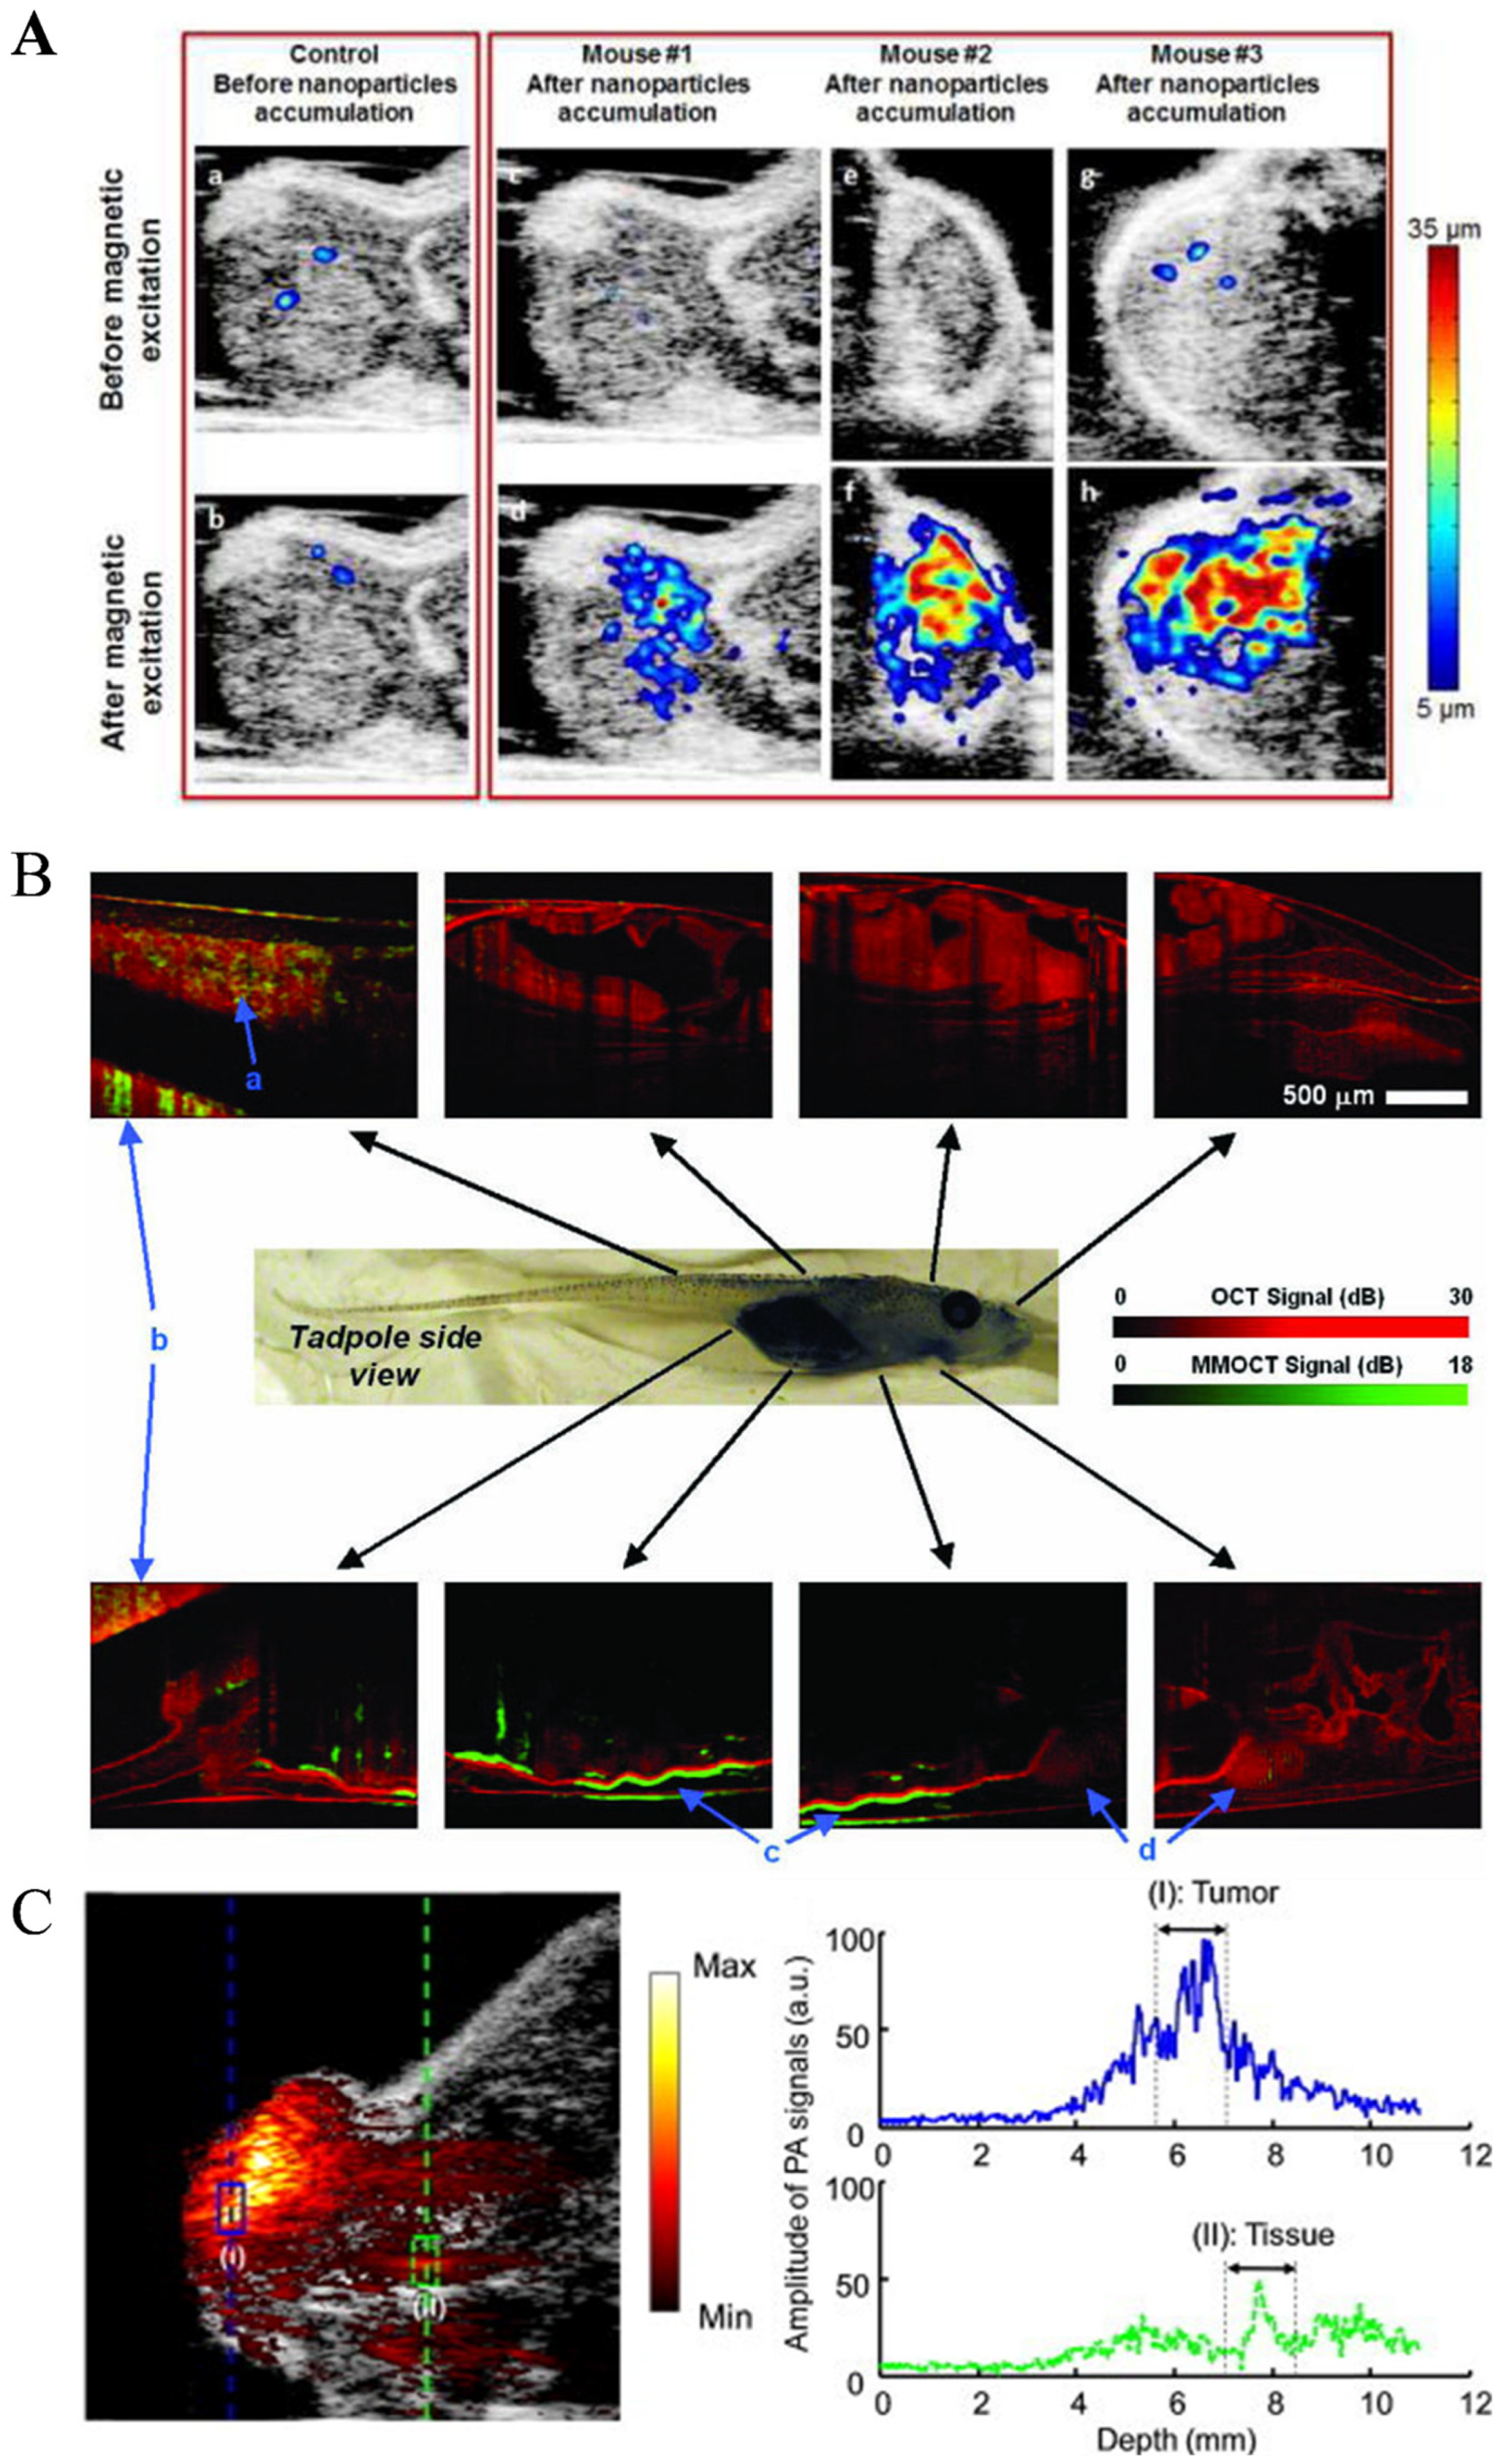

2.5.1. Photoacoustic Imaging (PAI)

2.5.2. Magnetomotive Assisted Imaging

- Yan, Y.; Jing, W.; Mehrmohammadi, M. Photoacoustic imaging to track magnetic-manipulated micro-robots in deep tissue. Sensors 2020, 20, 2816. [Google Scholar] [CrossRef]

- Li, D.; Zhang, Y.; Liu, C.; Chen, J.; Sun, D.; Wang, L. Review of photoacoustic imaging for microrobots tracking in vivo. Chin. Opt. Lett. 2021, 19, 111701. [Google Scholar] [CrossRef]

- Yan, Y.; Mehrmohammadi, M.; Jing, W. Non-invasive photoacoustic imaging of magnetic microrobot through deep non-transparent tissue. In Proceedings of the 2020 International Conference on Manipulation, Automation and Robotics at Small Scales, IEEE, Toronto, ON, Canada, 13–17 July 2020; pp. 44–45. [Google Scholar] [CrossRef]

- Xie, L.; Pang, X.; Yan, X.; Dai, Q.; Lin, H.; Ye, J.; Cheng, Y.; Zhao, Q.; Ma, X.; Zhang, X.; et al. Photoacoustic imaging-trackable magnetic microswimmers for pathogenic bacterial infection treatment. ACS Nano 2020, 14, 2880–2893. [Google Scholar] [CrossRef] [PubMed]

- Aziz, A.; Nauber, R.; Iglesias, A.S.; Tang, M.; Ma, L.; Liz-Marzán, L.M.; Schmidt, O.G.; Medina-Sánchez, M. Nanomaterial-decorated micromotors for enhanced photoacoustic imaging. J. Micro-Bio Robot. 2023. [Google Scholar] [CrossRef]

- Wu, Z.G.; Li, L.; Yang, Y.R.; Hu, P.; Li, Y.; Yang, S.Y.O.; Wang, L.V.; Gao, W. A microrobotic system guided by photoacoustic computed tomography for targeted navigation in intestines in vivo. Sci. Robot. 2019, 4, eaax0613. [Google Scholar] [CrossRef] [PubMed]